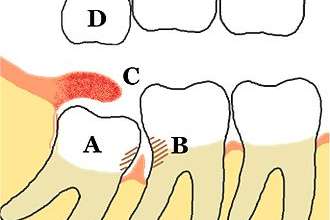

چه زمانی به پیوند استخوان دارید؟

اگر استخوان فک شما به اندازه کافی ضخیم نیست یا خیلی نرم است، ممکن است قبل از جراحی ایمپلنت دندان نیاز به پیوند استخوان داشته باشید. این به این دلیل است که عمل جویدن قوی دهان شما فشار زیادی به استخوان شما وارد می کند و اگر نتواند ایمپلنت را پشتیبانی کند، احتمالاً جراحی شکست می خورد. پیوند استخوان می تواند پایه محکم تری برای ایمپلنت ایجاد کند.

چندین ماده پیوند استخوان وجود دارد که می توان از آنها برای بازسازی استخوان فک استفاده کرد. گزینه ها ممکن است شامل پیوند طبیعی استخوان، مانند محل دیگری در بدن شما، یا پیوند استخوان مصنوعی، مانند مواد جایگزین استخوان باشد که می تواند ساختارهای حمایت کننده برای رشد استخوان جدید را فراهم کند. با پزشک خود در مورد گزینه هایی که برای شما مناسب تر است صحبت کنید.

ممکن است چندین ماه طول بکشد تا استخوان پیوند شده به اندازه کافی استخوان جدید برای حمایت از ایمپلنت دندانی رشد کند. در برخی موارد، شما ممکن است فقط به پیوند جزئی استخوان نیاز داشته باشید، که می تواند همزمان با جراحی ایمپلنت انجام شود. وضعیت استخوان فک شما نحوه انجام کار را تعیین می کند.

قرار دادن ایمپلنت دندان

در حین جراحی برای قرار دادن ایمپلنت دندان، جراح دهان شما برشی ایجاد می کند تا لثه شما باز شود و استخوان نمایان شود. سوراخ هایی در استخوان که در آن پست فلزی ایمپلنت دندان قرار می گیرد، حفر می شود. از آنجا که پست به عنوان ریشه دندان عمل می کند، در اعماق استخوان کاشته می شود.